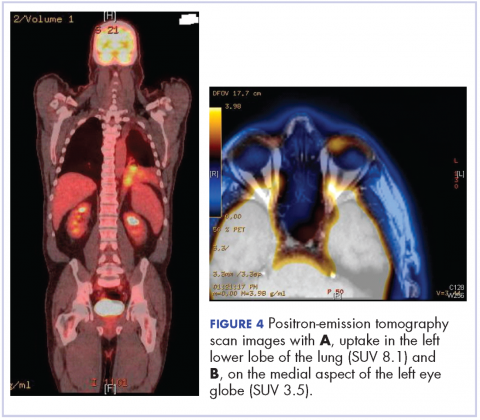

After the diagnosis, a chest X-ray showed that the patient had a left lower lung mass. The results of his physical exam were all within normal limits, with the exception of decreased visual acuity in the left eye. The results of his laboratory studies, including complete blood count and serum chemistries, were also within normal limits. Imaging studies – including a computed-tomography (CT) scan of the chest, abdomen, and pelvis and a full-body positron-emission tomography–CT scan – showed a hypermetabolic left lower lobe mass 4.5 cm and right lower paratracheal lymph node metastasis 2 cm with a small focus of increased uptake alone the medial aspect of the left globe (Figures 3 and 4).